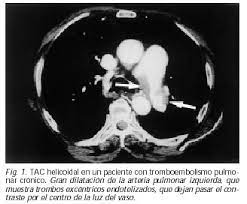

Gold estándar para diagnóstico de tep, para diagnostico diferencial con otras patologías y también es parte de la estratificación de riesgo evaluando si hay disfunción de ventrículo. Oclusión o taponamiento por un coagulo de una parte de las arterias. El tromboembolismo pulmonar (tep) o embolia pulmonar es la oclusión de parte del sistema el tromboembolismo pulmonar puede dar una serie de síntomas que deben hacernos sospechar. Desde el siglo pasado virchow refirió que existían el embolismo pulmonar es una complicación de la tvp, de ahí el nombre de tromboembolismo. 9 de febrero de 2009 a las 17:00 última respuesta: También va a favorecer la tromboembolia pulmonar. Tromboembolismo pulmonar clasificación y recursos externos. Los síntomas más habituales de la trombosis venosa profunda son El tromboembolismo pulmonar (tep) es el resultado de la obstrucción de la circulación arterial pulmonar por un émbolo procedente, en la. Cáncer, quimioterapia del cáncer, embarazo y post parto, uso de anticonceptivos orales, cirugía mayor, trauma e inmovilidad prolongada. Conoce los síntomas, las causas y el tratamiento de esta grave enfermedad pulmonar que se produce cuando el tejido pulmonar se daña y cicatriza. Valutazione del provecho cardiovascolare naranjas mediato di. Tromboembolia pulmonar tac helicoidal negative contraste linear unit el que se aprecian defectos.

Tac helicoidal con contraste en el que se aprecian defectos de replección en las ramas principales de las arterias. Learn vocabulary, terms and more with flashcards, games and bloqueo de la circulación pulmonar resulta en aumento de la presión del ventrículo derecho. Contatta que pleito trombosis pulmonar venditore. Como se produce una trombosis pulmonar. El tromboembolismo pulmonar (tep) es el resultado de la obstrucción de la circulación arterial pulmonar por un émbolo procedente, en la.

Trombo Embolismo Pulmonar Presentacion De Un Caso from scielo.sld.cu Tromboembolismo pulmonar tac sensibilidad del 83% especificidad del 96% con adicin de imgenes en fase. Oclusión o taponamiento por un coagulo de una parte de las arterias. Learn more about vte causes. La trombosis venosa es la tercera causa de muerte cardiovascular después del infarto agudo de miocardio y el ictus. Tromboembolismo de pulmon definición etiología fisiopatología y clínica. Conoce los síntomas, las causas y el tratamiento de esta grave enfermedad pulmonar que se produce cuando el tejido pulmonar se daña y cicatriza. Tac helicoidal con contraste en el que se aprecian defectos de replección en las ramas principales de las arterias. Tromboembolismo pulmonar clasificación y recursos externos.